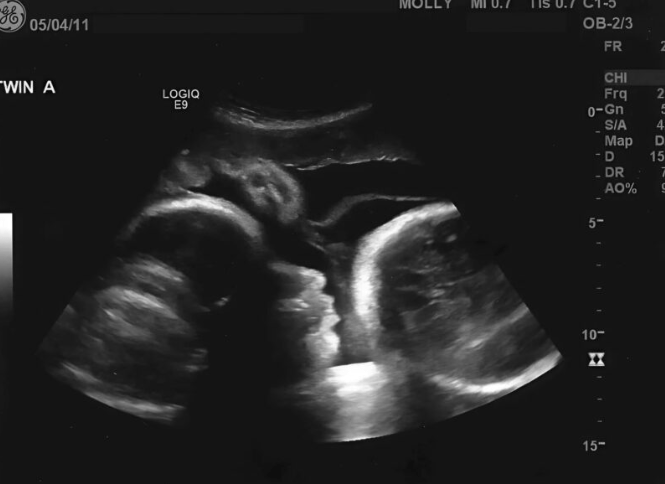

Konačno, Larisa je odlučila da ode kod ginekologa. Bilo je vreme da sazna tačno stanje. Iako je bila potpuno uverena da je trudna, pregled je otkrio nešto sasvim drugačije. Na ekranu je bilo jasno da nije bilo bebe, već nešto što nije imalo nikakve veze sa trudnoćom. Lekar je brzo shvatio da njeni simptomi nisu rezultat trudnoće, već ozbiljnog medicinskog problema koji je uzrokovao rast njenog stomaka.